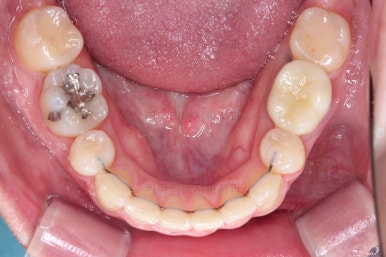

동래교정치과 마무리 사진입니다.

종료 이후에는 어금니의 기존 크라운 보철이 오래되고 탈이나서 재보철을 해주었습니다.

앞니는 비뚠채로 장기간 마모가 되어온 터라 형태가 부적절하긴 한데요.

보철로 마무리하기 보다는 최대한 자연스럽게 시리지 않는 선에서 다듬어 드리고 마무리를 했습니다.